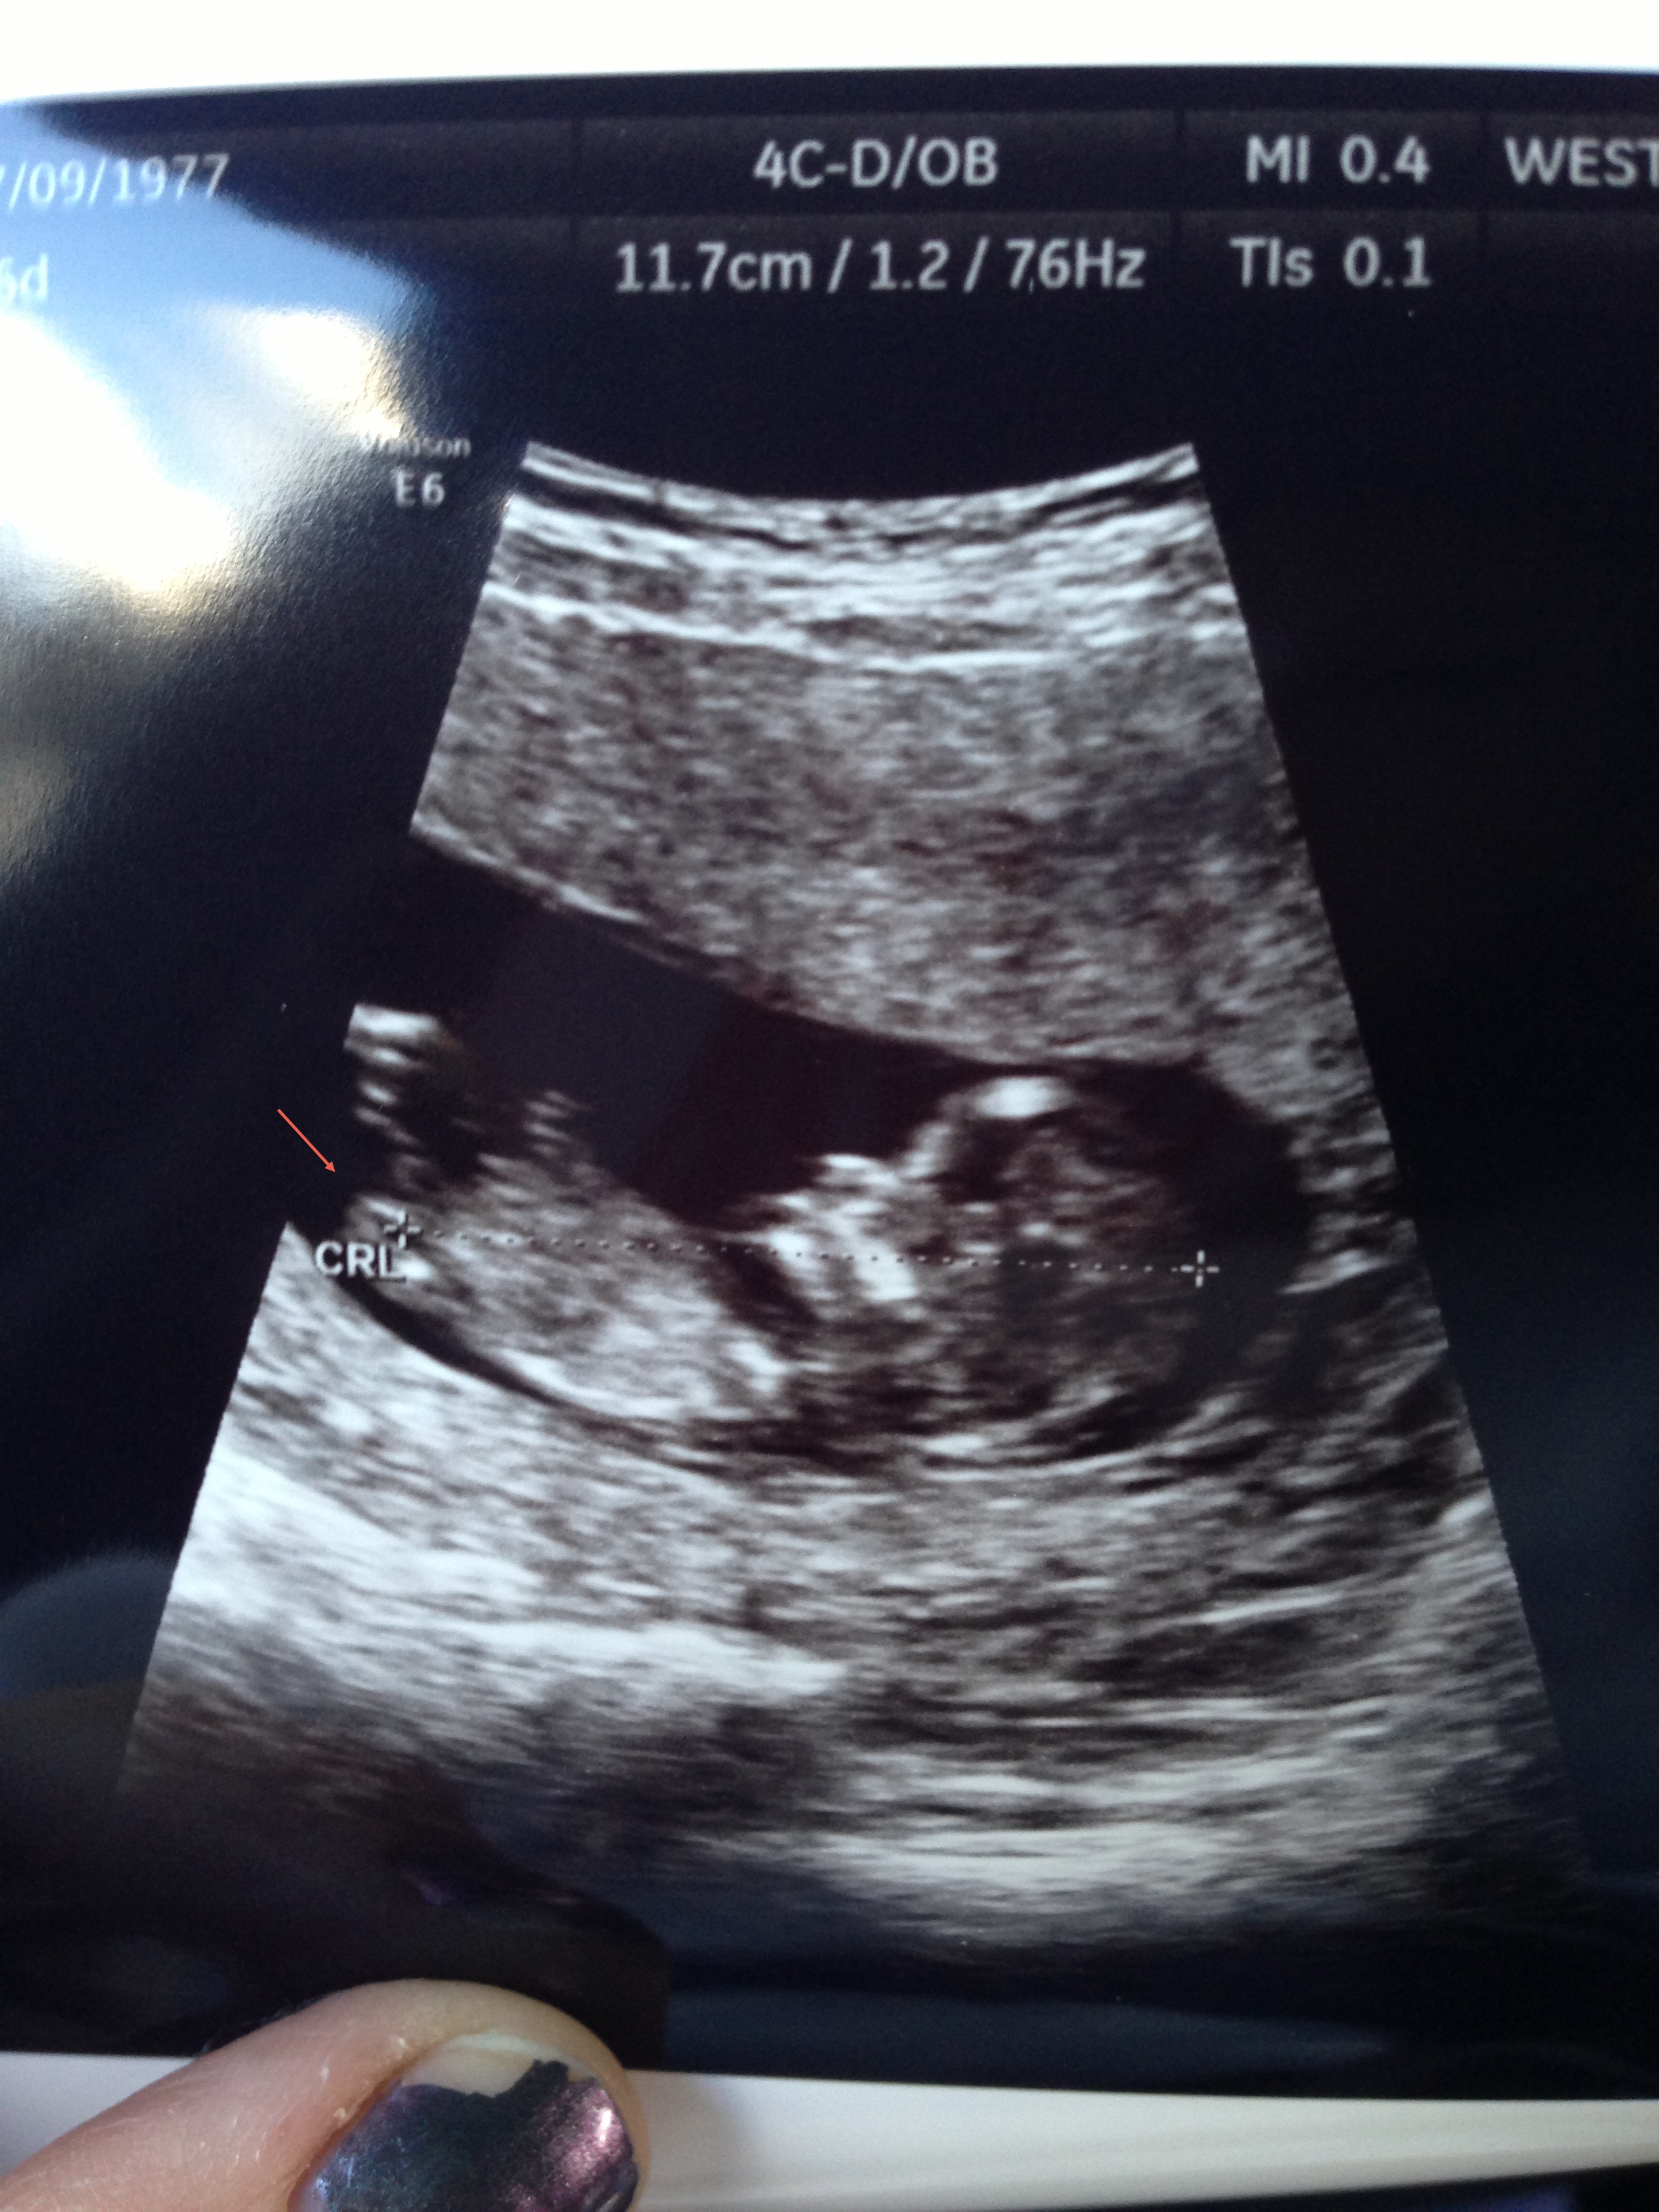

If so, i think its parallel with the spine but ramzi theory says if head is on the right side of pic at 12 weeks, its a boy. Thoughts?

Sorry i can't be sure but did not want to read and run. I think nub theory is meant to be more reliable than Ramzi though.